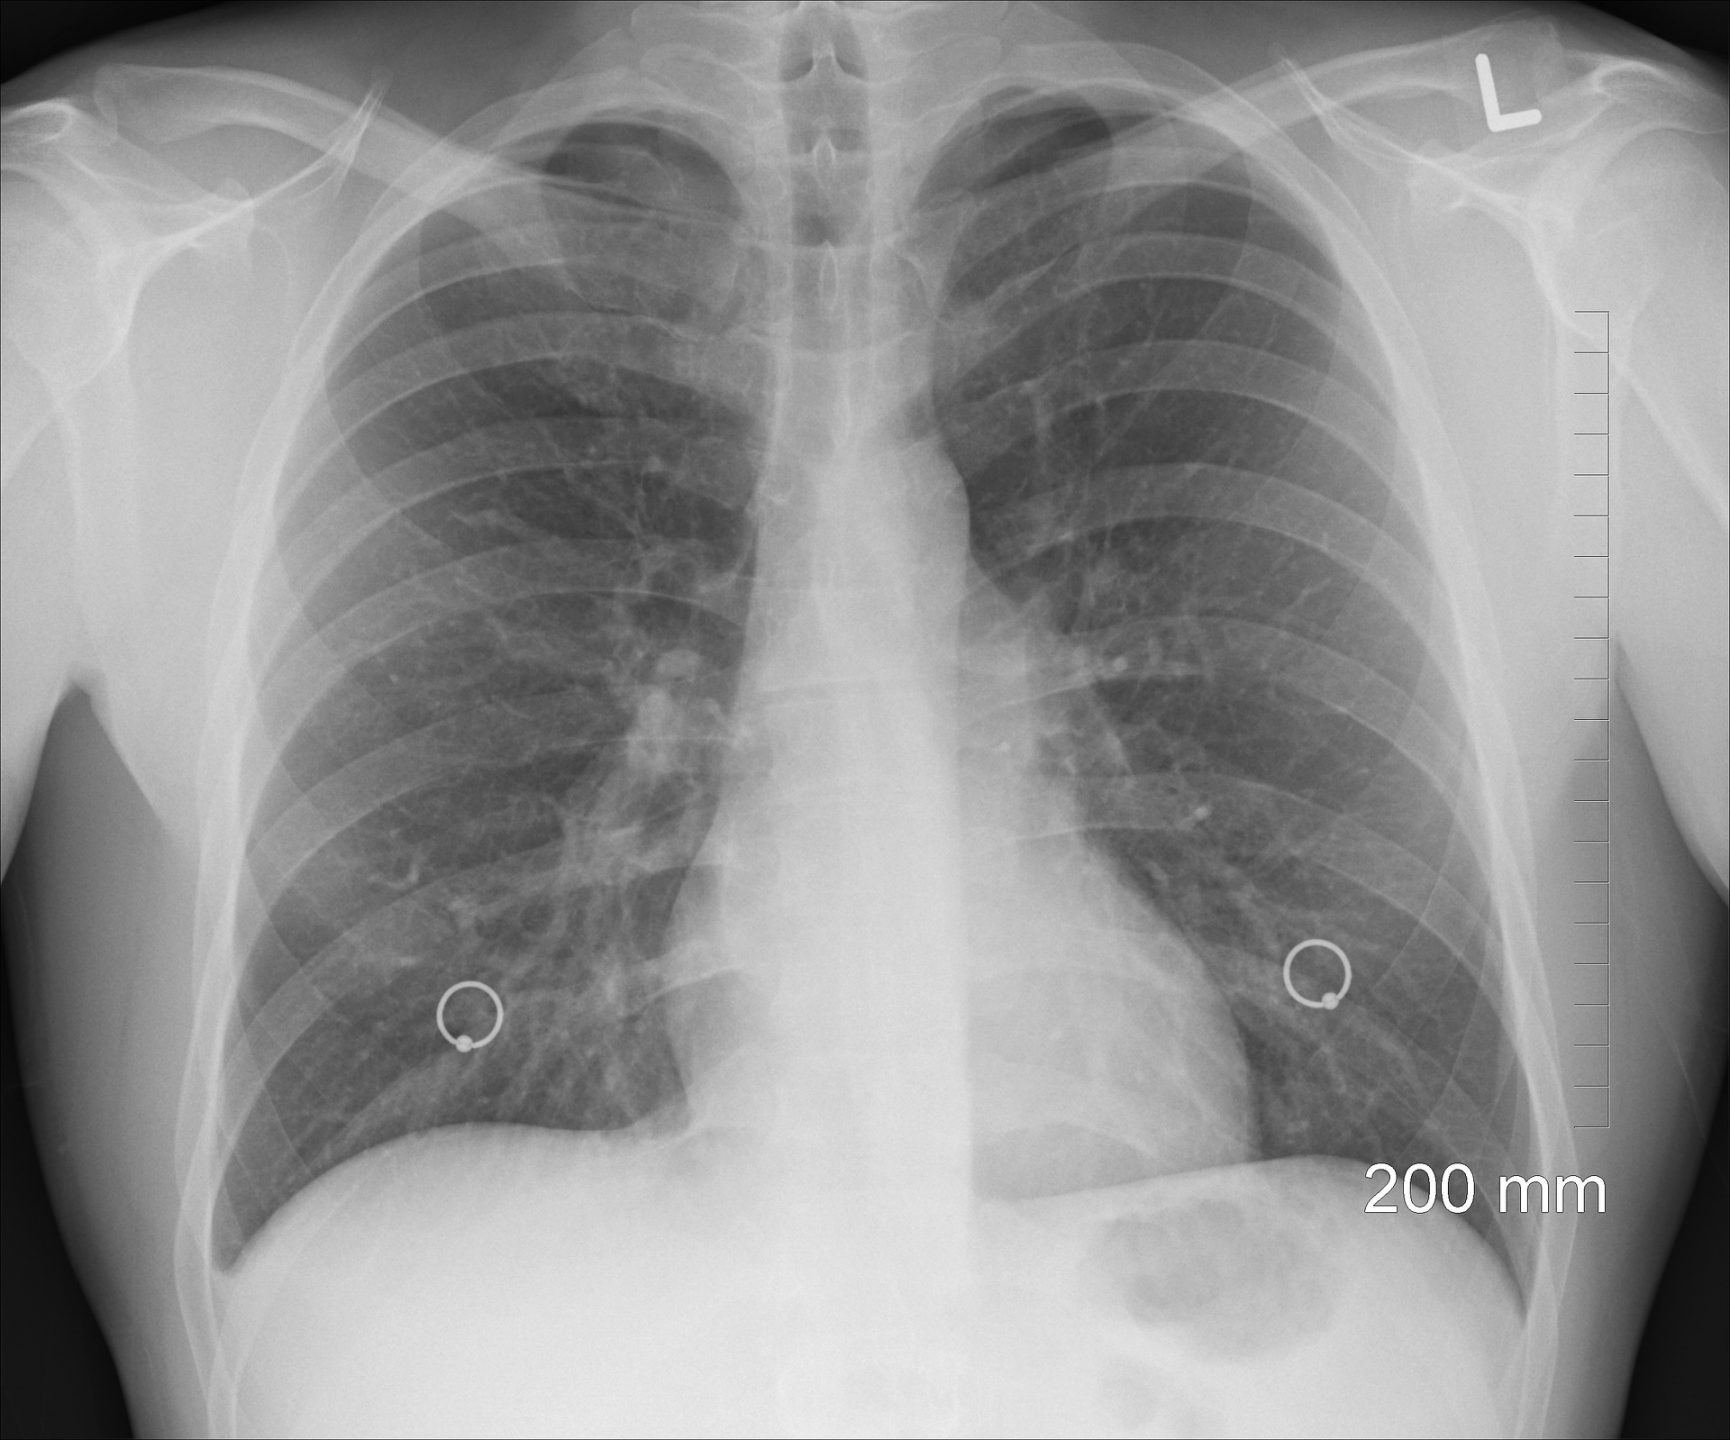

Bilde av lungene fra wikipedia.org

Våre lunger består av lungelapper. Den høyre lungen består av tre lapper og den mindre venstre består av to.